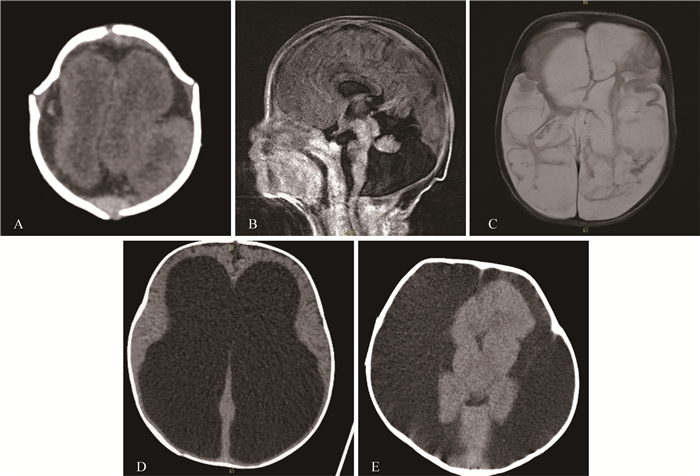

Fig 1 Imaging demonstrations of CNS malformations in the ≤ 1-year-old group A: CT revealed lissencephaly in a one-month-old infant; B: Dandy-walker malformation was found on sagittal MRI in a 1-month-old infant who died 3 months after birth; C: The cystic changes in bilateral cerebral parenchyma was found on MRI in a 2-month-old infant; D: The heavy hydrocephalus was found on CT in a 2-month-old infant who died after one-month treatment; E: The extent subdural effusion was found on CT for a 10-month-old infant who died one year after birth.